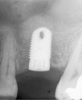

Once it is determined that the twist drill (2.1-mm diameter) is within 1 mm of the sinus floor, the second drill (2.8-mm diameter) and third drill (3.5-mm diameter), if desired, are used to penetrate to within 1 mm of the sinus floor (Figure 3). The amount of osteotomy widening is dependent upon tactilely perceived bone quality.

Figure 3  The osteotomy was completed with the 2.1-, 2.8-, and 3.5-mm twist drills without penetrating into the sinus.

Figure 3